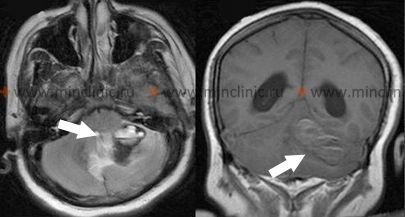

დაუყოვნებელი მართვის სტრატეგია იშემიური ინსულტის შემდეგ შიდა საძილე არტერიის (ICA) ტერიტორიაზე დიდად არის დამოკიდებული ინსულტის საწყის სიმძიმეზე და დაწყებიდან გასულ დროზე [1]. დიდი, დამანგრეველი ინსულტების შემთხვევაში, რომლებიც ვლინდება მძიმე დეფიციტით, როგორიცაა მჭიდრო ჰემიპლეგია, გლობალური აფაზია, ან ღრმა უგულებელყოფა/ანოსოგნოზია (რაც მიუთითებს ვრცელ ინფარქტზე, ხშირად მოიცავს შუა ტვინის არტერიის ტერიტორიის დიდ ნაწილს), მწვავე ფოკუსი გადადის ამ ტერიტორიაზე დაუყოვნებელი რეციდივის პრევენციიდან მხარდამჭერ ზრუნვაზე [1]. პრიორიტეტები მოიცავს პაციენტის სტაბილიზაციას, არტერიული წნევის ფრთხილად მართვას (ხშირად ნებადართულია პერმისიული ჰიპერტენზია თავდაპირველად, გარდა იმ შემთხვევისა, როდესაც არ ტარდება თრომბოლიზი ან თრომბექტომია), გართულებების პრევენციასა და მკურნალობას, როგორიცაა ცერებრალური შეშუპება, ასპირაციული პნევმონია და ღრმა ვენების თრომბოზი [1, 14].

ბოლოდროინდელი ინფარქტის ჰემორაგიული ტრანსფორმაცია არის პოტენციური გართულება CEA-ს შემდეგ, თუმცა შედარებით იშვიათია, თუ ოპერაცია სათანადოდ არის დაგეგმილი დროში და თავიდან აცილებულია პოსტოპერაციული ჰიპერტენზია [1, 9]. მიმდინარეობს დებატები CEA-ს ოპტიმალური დროის შესახებ მწვავე ინსულტის შემდეგ [2, 9]. მიუხედავად იმისა, რომ ოპერაციის გადადება რამდენიმე კვირით (მაგ., 2-6 კვირა) იძლევა ინფარქტის სტაბილიზაციის საშუალებას და ამცირებს სისხლდენის რისკს, გახანგრძლივებული დაყოვნება ზრდის განმეორებითი ინსულტის რისკს ჩარევამდე [2]. უფრო ადრეული ჩარევა (დღეებიდან 2 კვირამდე) შეიძლება განიხილებოდეს, განსაკუთრებით იმ პაციენტებისთვის, რომლებსაც აქვთ TIA-ები ან ძალიან მცირე ინსულტები, რომლებიც სტაბილიზირდნენ, ოპერაციის რისკების დაბალანსებით რეციდივის მაღალ ადრეულ რისკთან [2].

სიმპტომატური ინტრაკრანიალური სტენოზის (მაგ., საძილე სიფონის ან MCA ღეროს სტენოზი) მართვა ასევე მოითხოვს სპეციფიკურ მიდგომას [1, 3]. SAMMPRIS-ის მსგავს კვლევებზე დაყრდნობით [3], აგრესიული სამედიცინო მართვა აღემატება სტენტირებას პაციენტების უმეტესობისთვის მნიშვნელოვანი სიმპტომატური ინტრაკრანიალური სტენოზით [3]. ეს სამედიცინო მართვა მოიცავს ორმაგ ანტითრომბოციტულ თერაპიას (DAPT - ტიპიურად ასპირინი და კლოპიდოგრელი) საწყისი პერიოდის განმავლობაში (მაგ., 90 დღე), რომელსაც მოსდევს ერთიანი ანტითრომბოციტული თერაპია გრძელვადიანად, არტერიული წნევის და ქოლესტერინის ინტენსიურ კონტროლთან ერთად [3]. გრძელვადიანი ანტიკოაგულაცია (ვარფარინი) ზოგადად *არ* არის რეკომენდებული ინტრაკრანიალური ათეროსკლეროზული სტენოზისთვის სისხლდენის გაზრდილი რისკისა და ანტითრომბოციტულ საშუალებებზე დადასტურებული უპირატესობის არარსებობის გამო [1, 3].